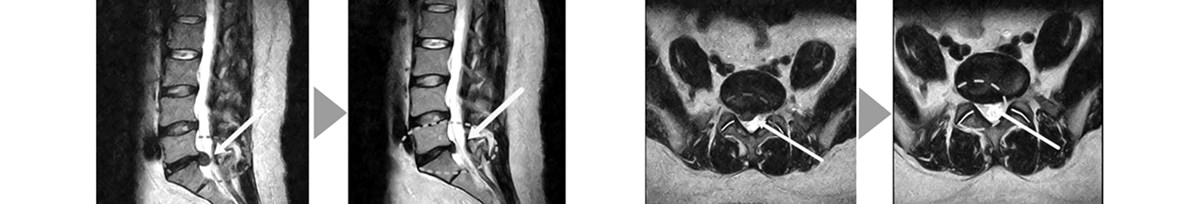

Percutaneous laser disc decompression (PLDD) is a type of surgery in which a laser probe is inserted into the intervertebral disc space and laser energy applied for achieving decompression and neuromodulation thereby relieving the pain.

PLDD is a minimally invasive procedure that falls into the category of percutaneous intervertebral surgeries with the aim to significantly reduce the patient’s pain and recover neurological deficit. It is performed under local anesthesia.

By a specially designed laser, with a coefficient of absorbing energy adjusted for soft discus tissue, specific amount of heat is sent to achieve the evaporation of the water from the disc without additional thermal damage thus achieving decompression and creation of a stable intradiscal scar that will prevent herniation from reoccurring.

Microsurgical precision is guaranteed by the technical characteristics of the special PLDD laser fibers, which allow for surgical effectiveness, ease of handling, and maximum safety. The laser fibers combination with the microsurgical PLDD enables a very precise and accurate access and intervention to sensitive areas like the cervical and lumbar disc zones on the basis of clinical therapeutic needs.PLDD laser treatments are mostly used after non-successful conventional therapeutic options under strict MRT / CT control.